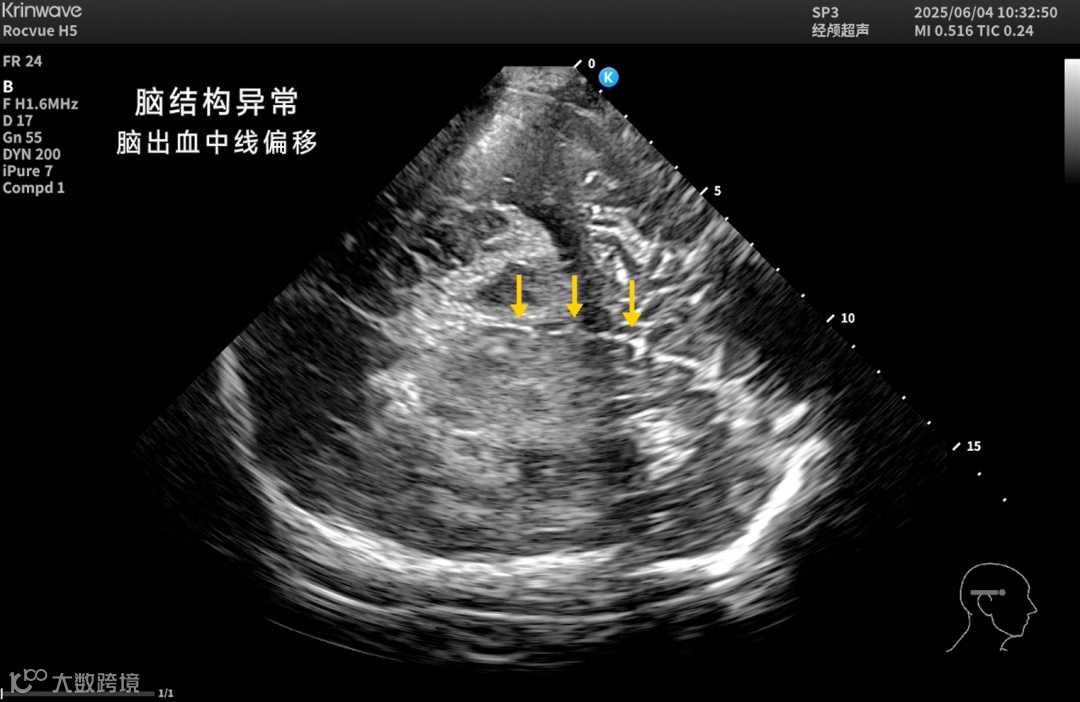

颅脑一直是超声成像的难题——

颅骨厚、衰减强、反射乱,声能传输率不足10%。

让超声在颅脑领域真正“看得见、看得清”。

● 神经重症监测

床旁实时评估颅内压、脑血流动力、脑水肿及血肿变化;

● 脑卒中防治

实现院前识别、院中动态监测与干预评估;